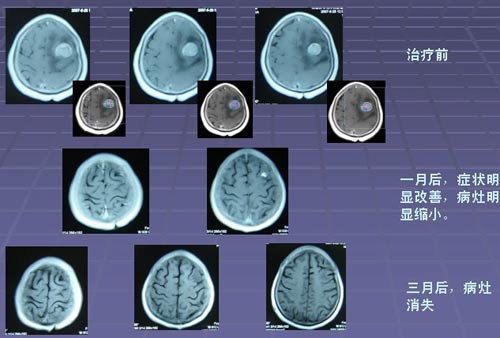

在大多数人的意识里,癌症就代表着绝望与死亡。但据中国工程院院士、中国医学科学院肿瘤医院孙燕教授2011年介绍:肿瘤科医生患癌后, 80%都得到了治愈(5年生存)特别是一些发生 肺癌脑转移 ,目前依然带瘤生存。。而国家癌症中心全国肿瘤防治研究办公室 ...